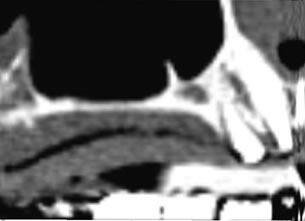

症例1 : 上下顎無菌顎症例

69歳、男性。

• 上顎は両側サイナスリフトと同時に即時荷重を行った。

• 下顎は抜歯即時埋入即時荷重を行った。

• 最終補綴物は、チタンのP.I.B.とM.B.のコンビネーションで修復した。

• 本症例の要旨は第39回日本口腔インプラント学会(大阪)にて症例報告した。